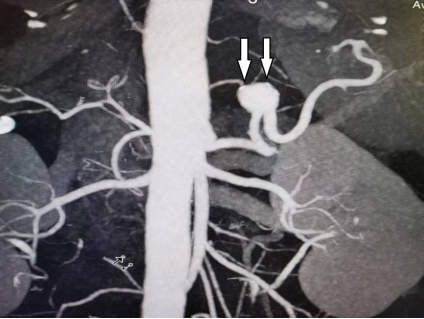

CTA显示脾动脉主干动脉瘤形成,白箭头所指为脾动脉上动脉瘤体。